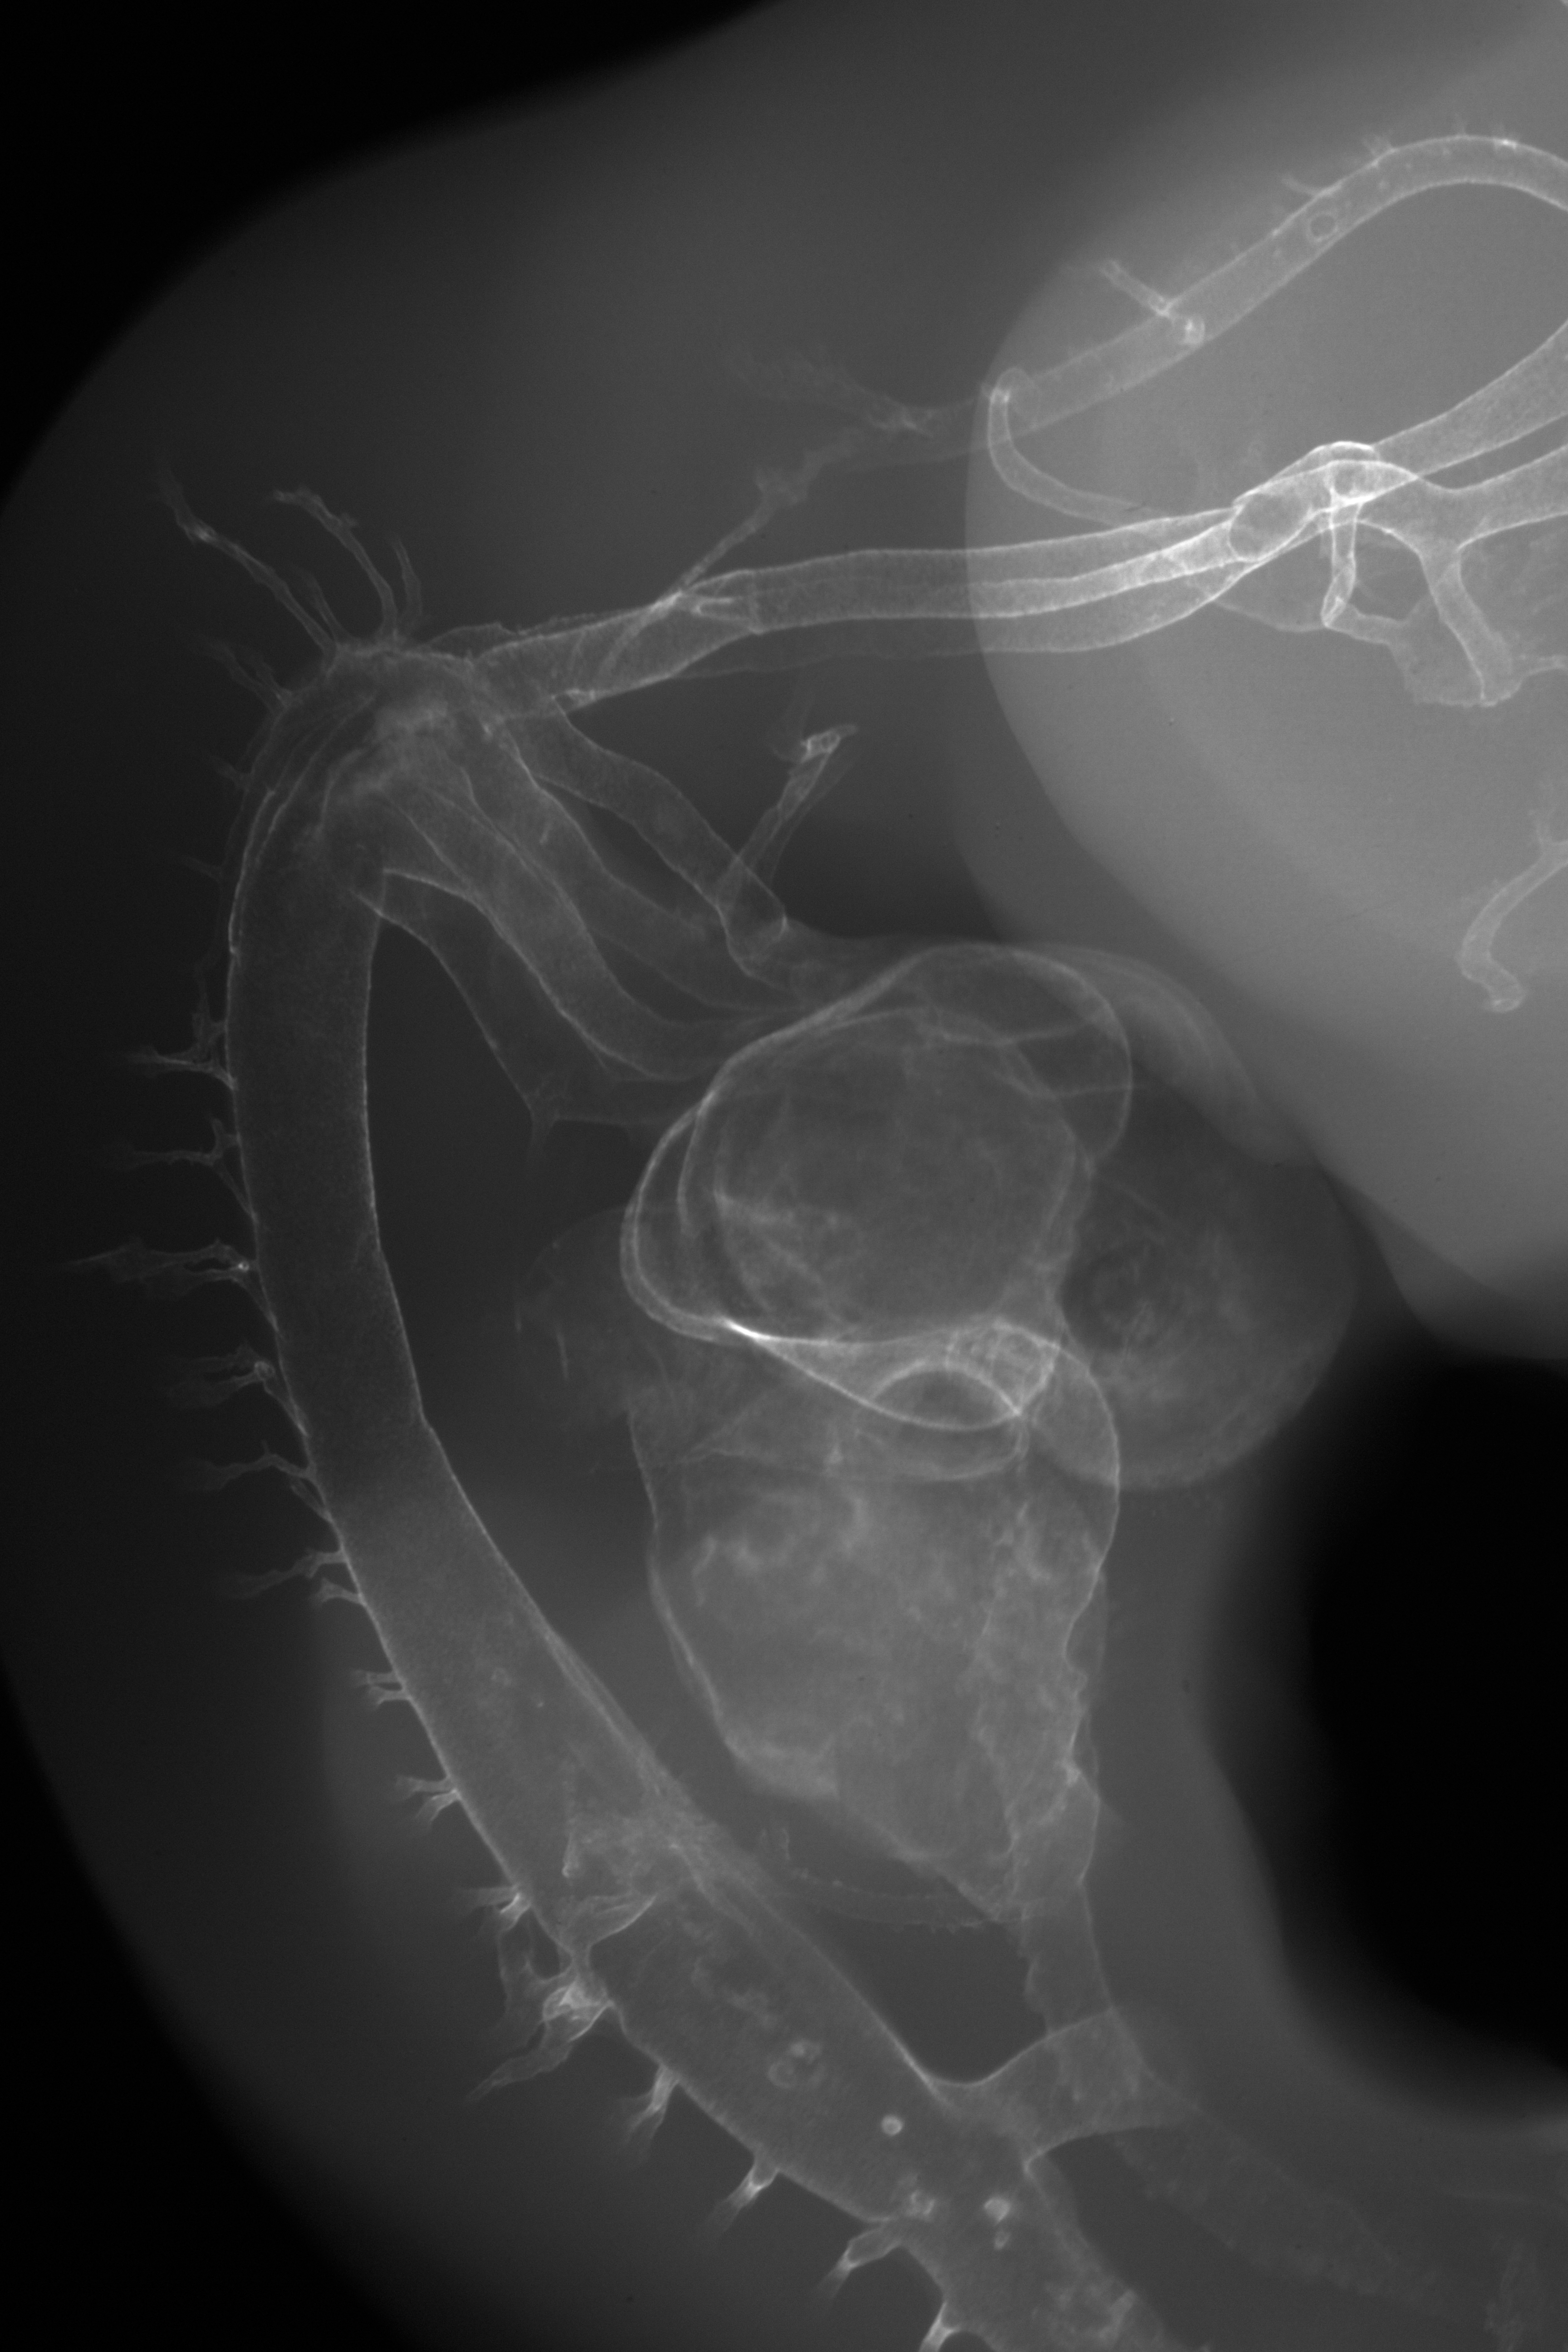

Chick Embryo Microangiography

Hamburger-Hamilton (HH) Stage 26 (approx. 5 days)

X-Ray Micrographs